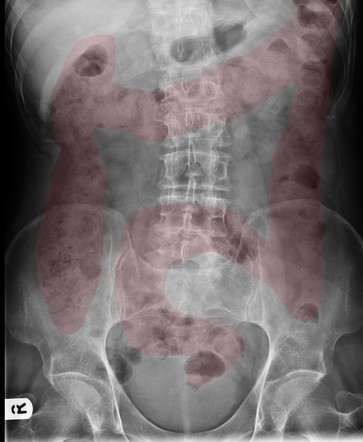

Bác sĩ đã cho bà mẹ xem hình ảnh chụp X-quang ổ bụng của con gái bà, chỉ ra rằng ruột già đã bị chặn bởi phân và đó là lý do vì sao cô bé lại phải đối mặt với những cơn đau bụng dữ dội. Bác sĩ cho biết trước đây cũng từng gặp một số trường hợp tương tự ở những đứa trẻ cùng tuổi.

Hình mang tính minh họa.